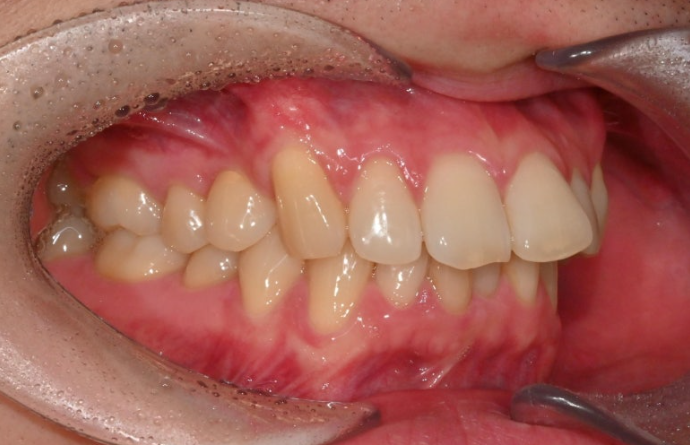

25.12

어금니 교합은 1급 교합관계를 보입니다.

앞니 뻗침은 좋아졌네요.

이제 전후 비교 보겠습니다.

25.02~25.12